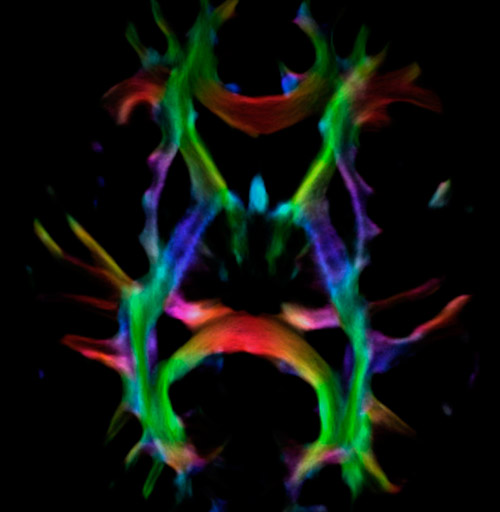

DEC TDI: directionally encoded color track-density imaging

CSD of multishell DWI results in the white matter FOD at each voxel. Unlike the conventional diffusion tensor model, this approach enables accurate modeling of multiple fiber populations within a single voxel.

Crossings of the corpus callosum, corticospinal tracts, and the superior longitudinal fasciculus are shown.

Crossing fibers of the corpus callosum bordered by the superior longitudinal fasciculus as well as within in the pons.

Super-resolution directionally encoded color track-density imaging overlaid on T1-weighted structural MRI.